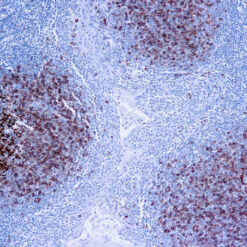

| Positive Control Tissue | Prostate carcinoma |